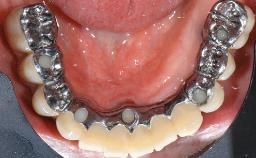

A male patient had lost teeth 11 and 22 as a result of a bicycle accident at age 14. In his adolescent years, a removable prosthesis had replaced the missing teeth. At age 21, the patient was referred by his dentist to the university clinic for treatment of the missing teeth 11 and 22 with implants. He was in good health and a nonsmoker. The absence of teeth 11 and 22 over many years had led to significant atrophy of the alveolar ridge, particularly at site 11. As a first step, the alveolar ridge was augmented using a block graft to replace the lost bone. A Straumann SP implant (diameter 4.1 mm, length 12 mm; Institut Straumann AG, Basel, Switzerland) and a Straumann Narrow Neck implant (length 10 mm) were inserted in the correct location and axial position at sites 11 and 22, respectively, six months later. After three months of healing and subsequent reentry, the patient returned to the referring dentist to receive the prosthetic restoration. The patient was seen again six months after the restoration had been placed. The frontal view showed a high smile line, an irregular gingival profile, and a bluish-gray tinge to implant crowns 11 and 22 compared to the natural dentition.